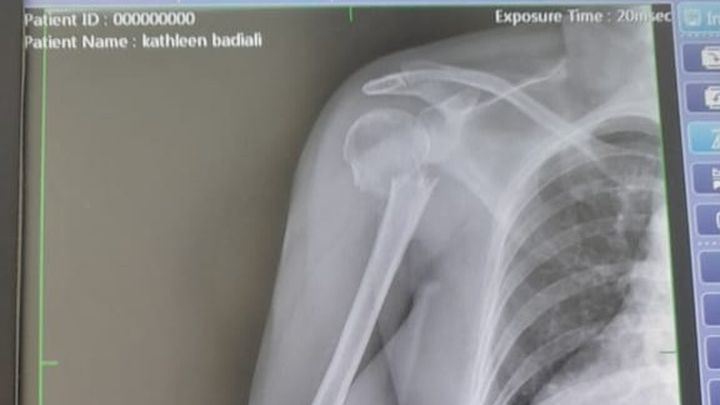

Last week I left for a 3-week trip to the US and she agreed to house/pet sit for me. A few days in, she slipped on a wet tile in my house and badly broke her right arm. With the help of several friends, we were able to get her to the hospital but upon arrival, they told her that they couldn't do surgery if she didn't have the cash to pay up front (they need ~$10K for the surgery alone).

Because she's not a CR resident, she can't be treated in the public hospital. She doesn't have travel or international health insurance to cover a private hospital. And because she's so badly injured, it's not safe for her to fly back to the US to have the surgery, and most likely the airlines wouldn't let her fly in her condition anyway.

She is in desperate need of our help. She's in excruciating pain and needs this surgery ASAP not only to relieve the pain but to give her the best chance at a complete recovery.